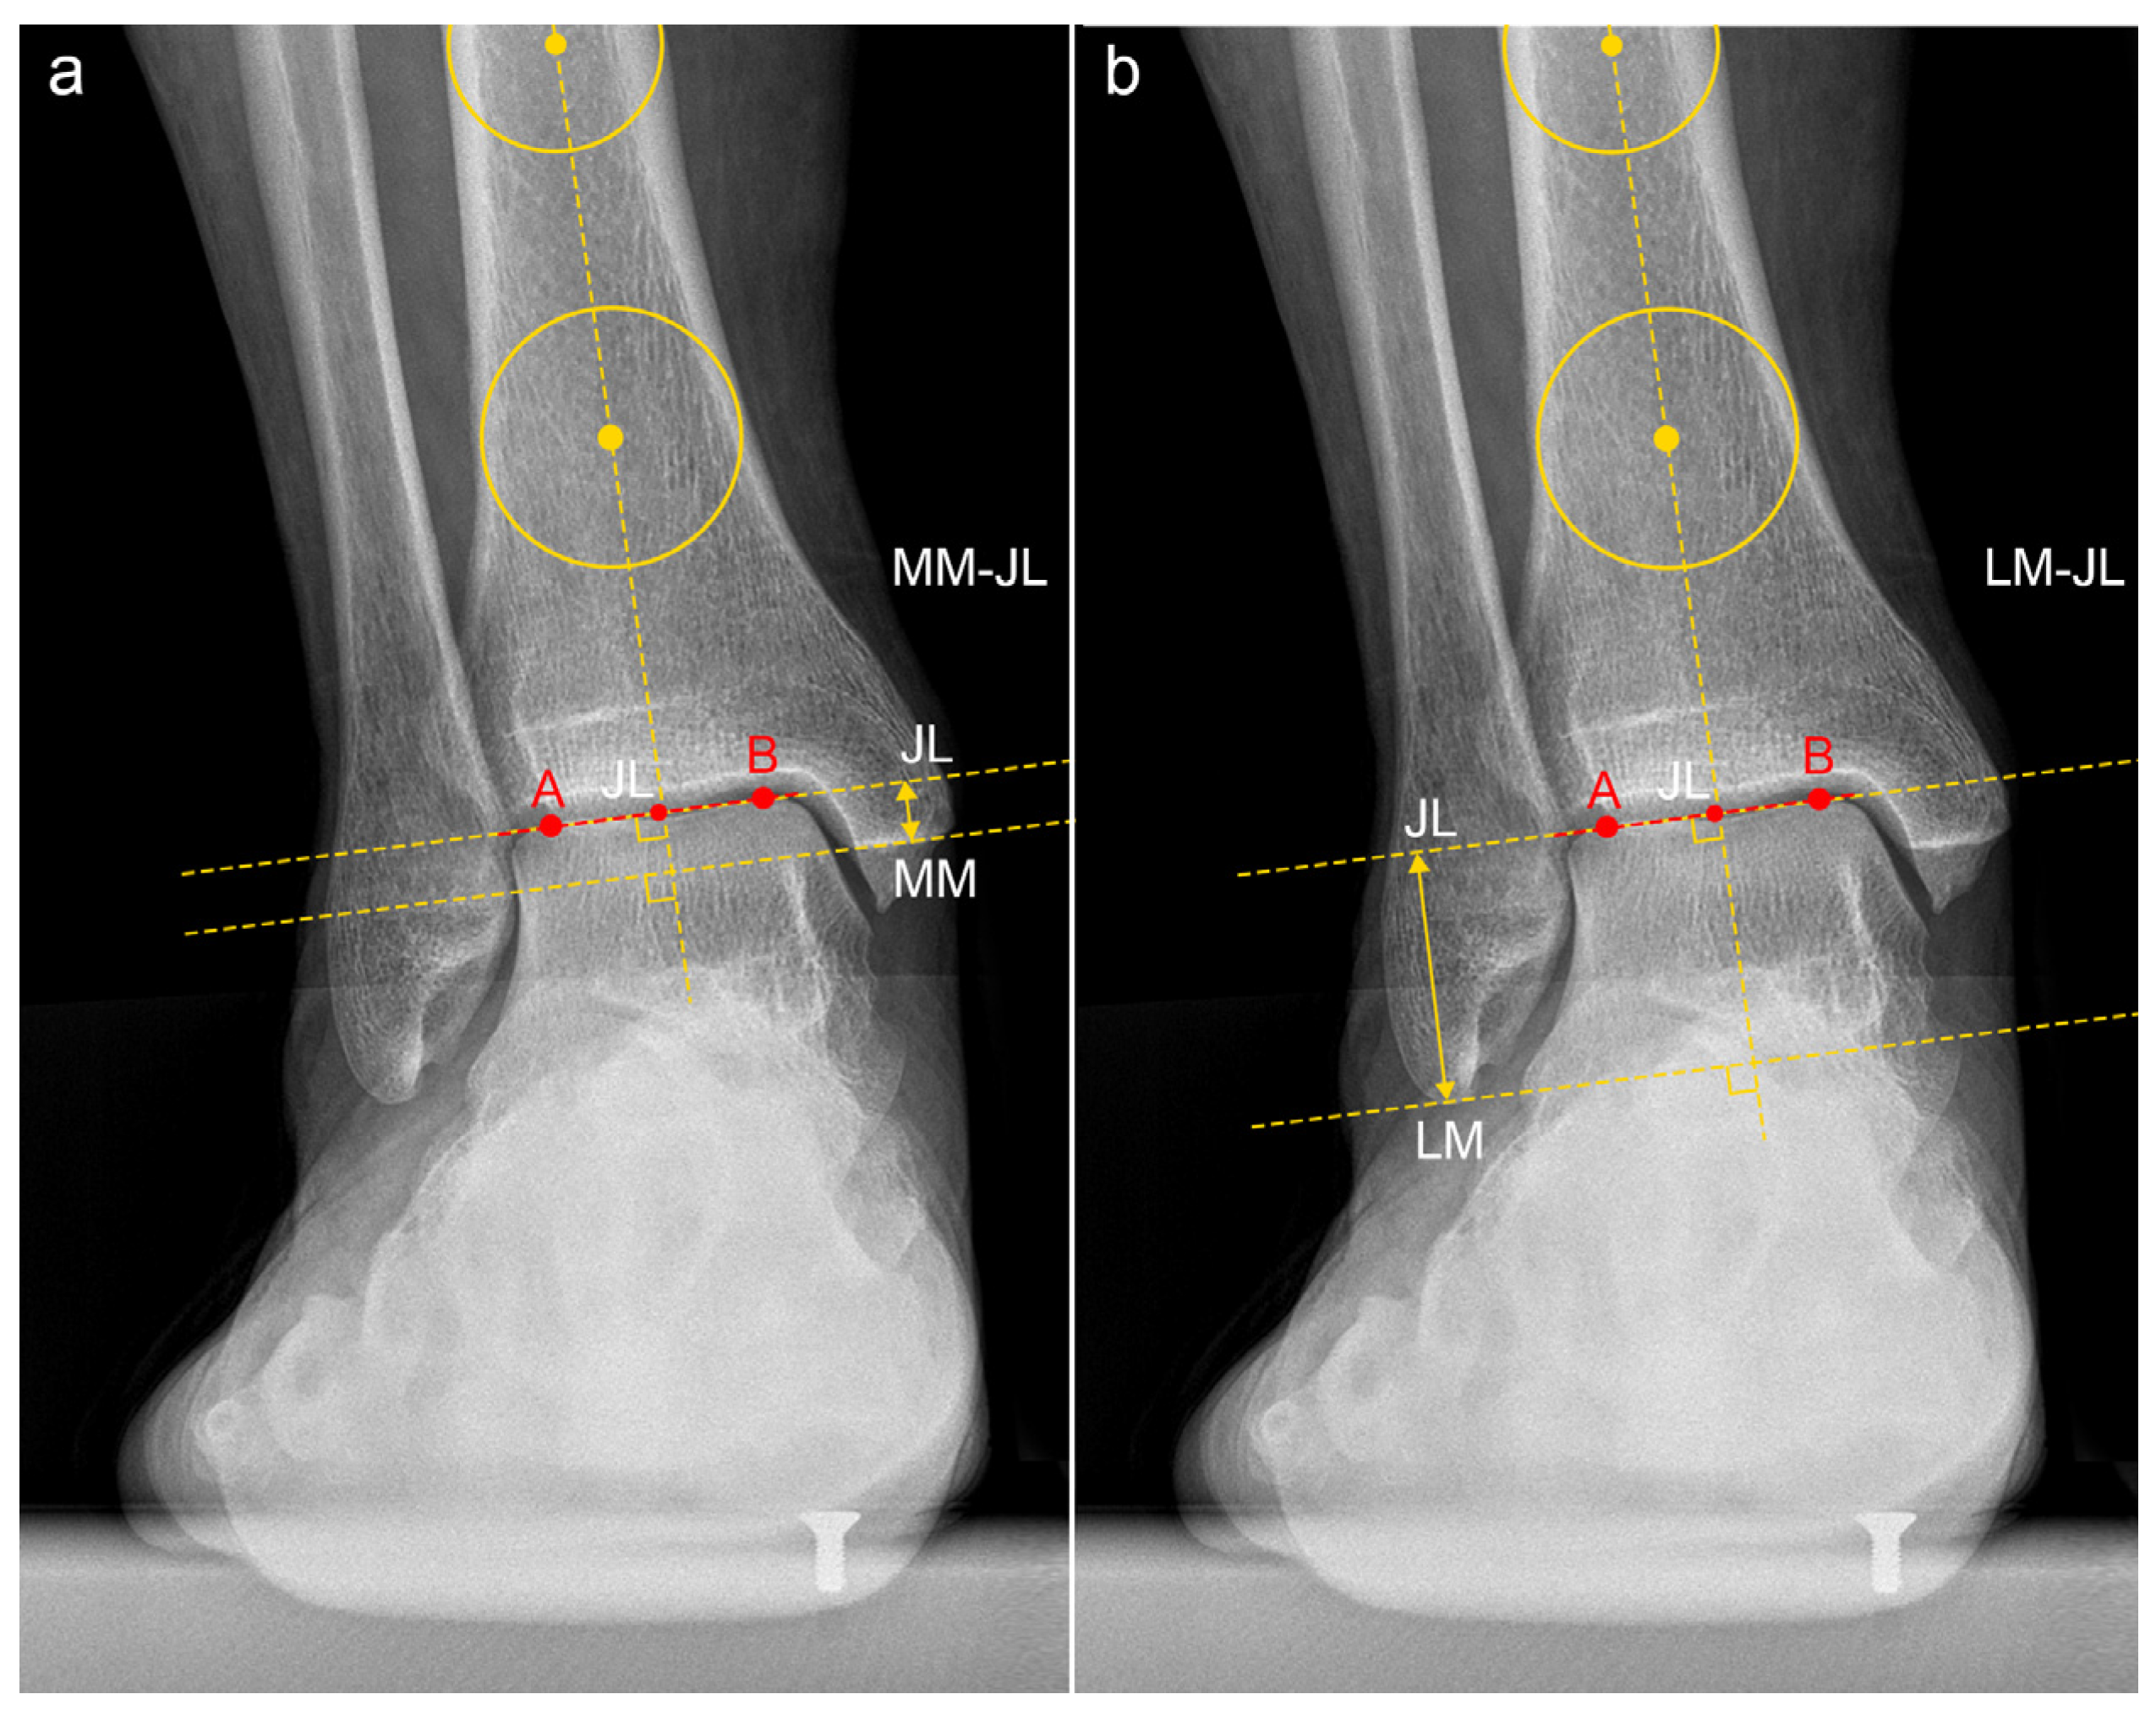

| JLHR 1 | 2.23 ± 0.54 | 1.94 | 1.64–3.44 | 24.3% |

| LM-JL 2 distance | 2.30 ± 0.39 cm | 2.12 cm | 1.78–3.19 cm | 17.0% |

| MM-JL 3 distance | 1.21 ± 0.30 cm | 1.11 cm | 0.89–1.78 cm | 24.9% |

| CS-JL 4 distance | 3.82 ± 0.51 cm | 3.87 cm | 2.94–4.53 cm | 13.4% |

| JLHR 1 (contralateral) | 1.95 ± 0.54 | 1.92 | 1.49–3.54 | 27.7% |

| LM-JL 2 distance (contralateral) | 2.21 ± 0.26 cm | 2.12 cm | 1.84–2.81 cm | 11.8% |

| MM-JL 3 distance (contralateral) | 1.00 ± 0.20 cm | 0.92 cm | 0.76–1.42 cm | 20.3% |

| CS-JL 4 distance (contralateral) | 4.04 ± 0.32 cm | 4.06 cm | 3.46–4.53 cm | 7.8% |